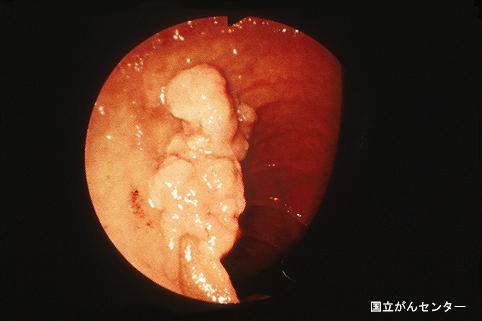

症例提示(所在地,施設名等): 東京都・ 国立がんセンター中央病院と九州がんセンターの共同作成

症例登録日 2003/10/30

画像数 15

性別 男性

年齢 75-79

取得年代 1990-1994

画像ID:6080

[ 画像ID:6080 ]

疾患(病理主体)の分類悪性上皮性腫瘍/腺癌

部位(臓器別)十二指腸/下行脚

検査方法内視鏡

腫瘍の肉眼分類0型(表在型)/I型(Is)

病変の最大径(ミリ)25〜29

腫瘍の深達度m

多発腫瘍(同一臓器)

多重腫瘍(他臓器)有(異時性)